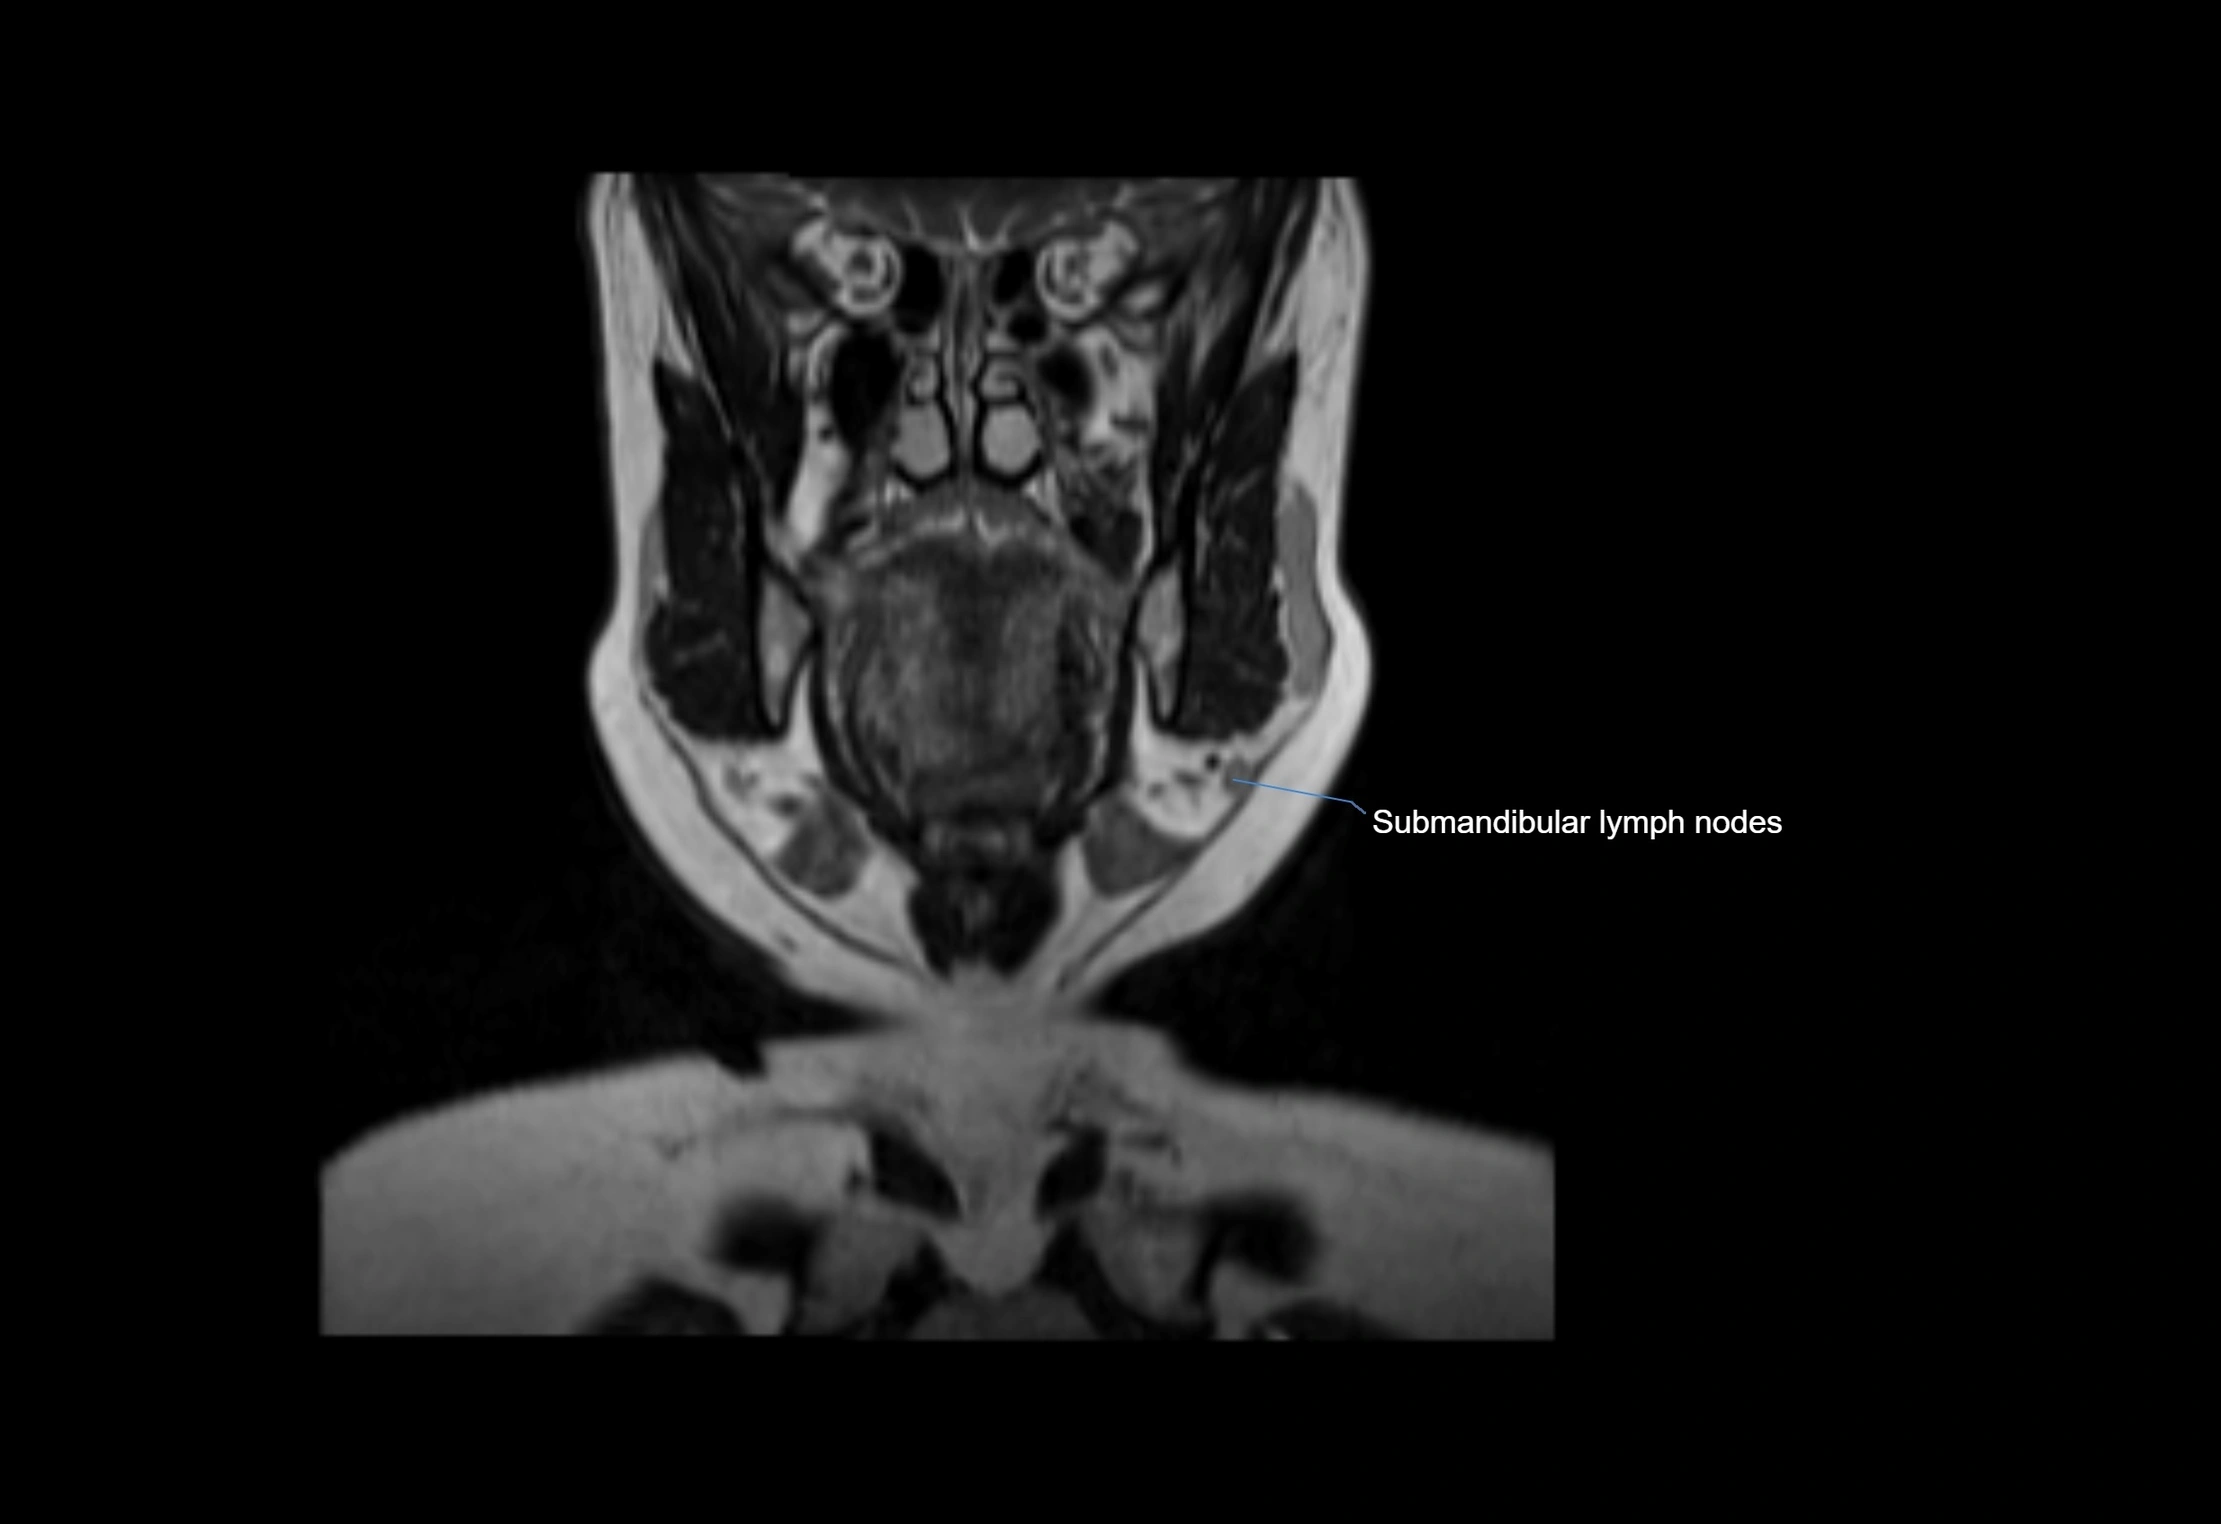

MRI Appearance

T1-weighted images:

• Normal accessory nodes appear as small, oval hypointense to intermediate signal structures within subcutaneous fat

• Surrounded by hyperintense fat, enhancing contrast for visualization

• Pathological nodes may appear enlarged or rounded, sometimes with cortical thickening

T2-weighted images:

• Nodes show intermediate signal, with surrounding fat bright

• Useful for detecting edema, inflammation, or infiltration

• Fatty hilum may appear slightly hyperintense relative to cortex

MRI images